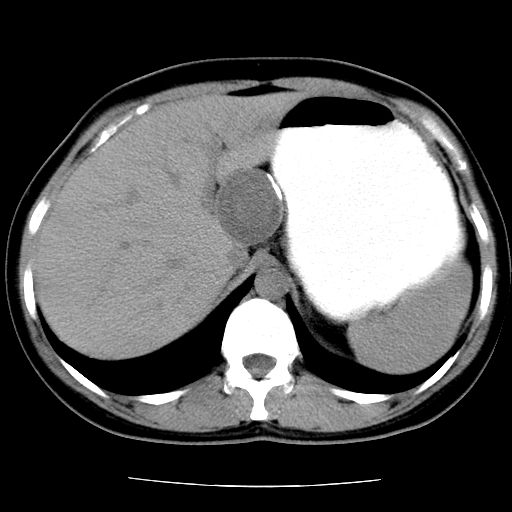

标题: CT16892:女40Y,急性阑尾住院!

女40y,急性阑尾住院!术前发现请会诊!

考虑门静脉瘤样扩张可能,建议增强扫描

胰头假性囊肿也有可能,建议增强

病灶位于门静脉的位置 ,有层面显示血管夹层样改变 ,考虑是门静脉瘤样病变1

病灶位于门静脉的位置 ,有层面显示血管夹层样改变 ,考虑是门静脉瘤样病变,建议进一步增强ct检查。

肝胃间隙良性占位病变,考虑囊肿可能性,不除外神经源性肿瘤,建议增强

肝门区囊性占位,壁有钙化,考虑良性。来源难定。